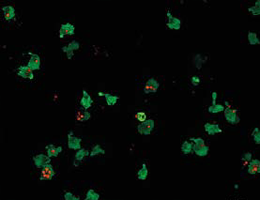

“We developed a procedure which allowed us to specifically delete single genes in cultured human immune cells that closely resemble human monocytes. Using this system, we were able to identify, at the genetic level, the components responsible for signal transmission to, and activation of the NLRP3 inflammasome,” explains Moritz Gaidt, a doctoral student in Hornung’s group and first author of the new study. In this way, the team was able to analyze the secretion of IL-1 by human monocytes in unprecedented detail – and to define the mechanism that enables human NLRP3 to be activated in response to a single signal.

The researchers activated the TLR4 receptor by exposing their monocytes to bacterial lipopolysaccharide (LPS) – a complex molecule made up of sugars and fats, which is found on the surface of many pathogenic bacteria. They then showed that binding of LPS triggers the secretion of IL-1 via a previously unrecognized signal relay. “The activation of this new pathway explains why human monocytes do not need a second signal to secrete IL-1. Conversely, in mouse monocytes this particular pathway is not activated, so a second stimulus is required,” Veit Hornung explains. Moreover, while inflammasome activation in the mouse induces programmed inflammatory cell death, the pathway used in human monocytes does not. “We refer to this signal pathway as the alternative inflammasome, in order to distinguish it from previously described pathways,” says Hornung. “We believe that this signal pathway plays a critical role in inflammatory processes in humans.”